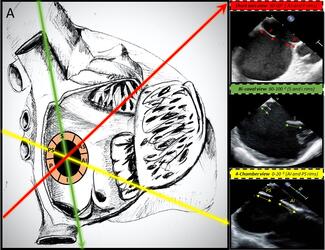

The balloon deflection technique has been reported to be helpful in wiring of angulated side branch. The authors' case illustrates the use of this technique in improving wire control in an angulated side branch, resulting in a successful...